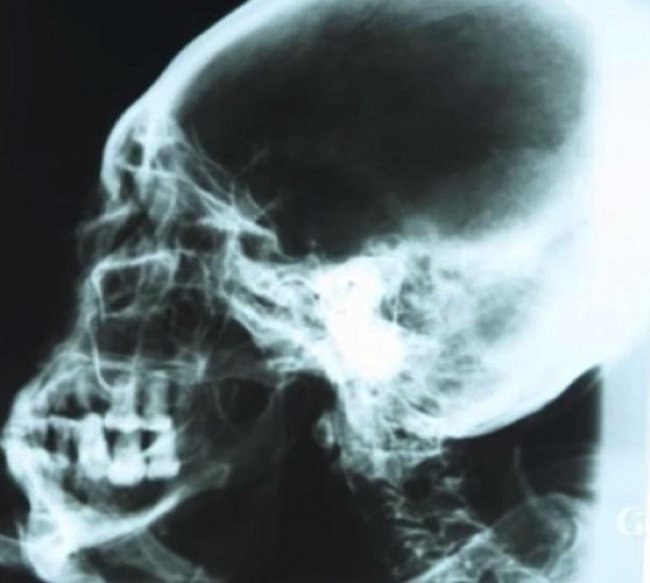

Рентгеновский снимок черепа мумии

Мумия похожа на гипсовую скульптуру, посыпана каким-то белым порошком. Но, как показал рентген и компьютерная томография, это отнюдь не изваяние. Внутри — скелет, останки внутренних органов. Посредством радиоуглеродного анализа установлено, что тканям мумии 2300 — 2500 лет. Порошок, по мнению ученых, обладает бальзамирующими свойствами. Мумия обсыпана им для сохранности.

Пропорции тела у мумии в целом человеческие. В распрямленном состоянии ее рост составил бы 168 сантиметров. Очень странная голова с — удлиненным, вытянутым назад, черепом. Нос — крошечный, ушей — нет. Вместо них — едва заметные отверстия в черепе.